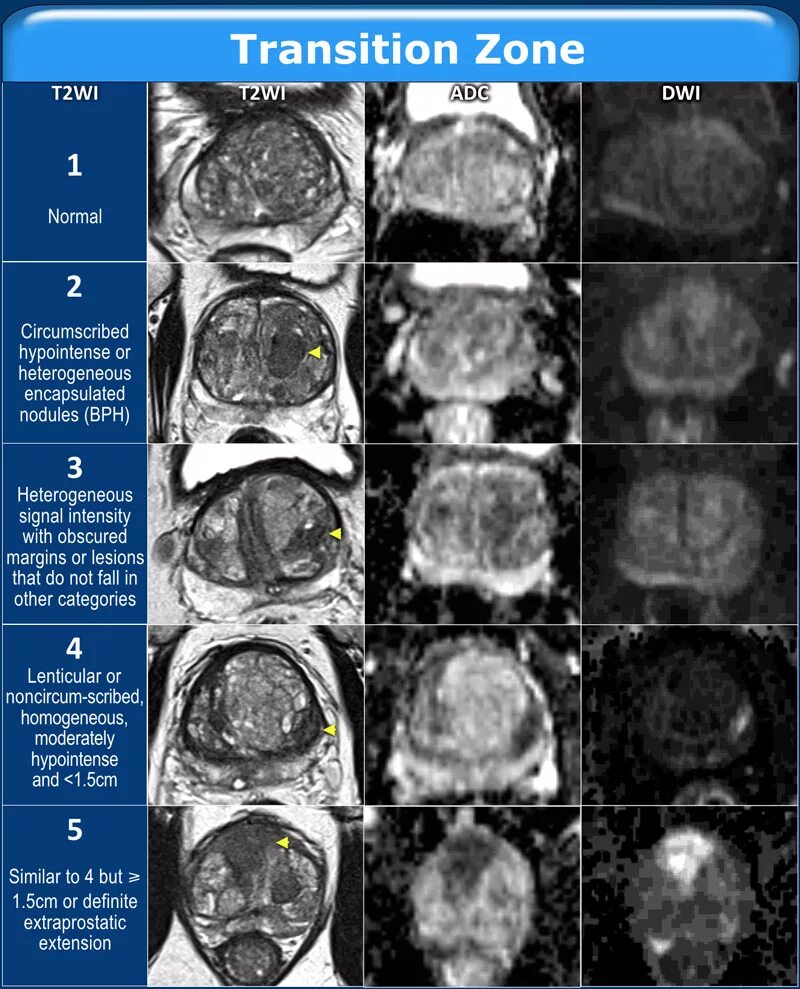

Pi rads 4